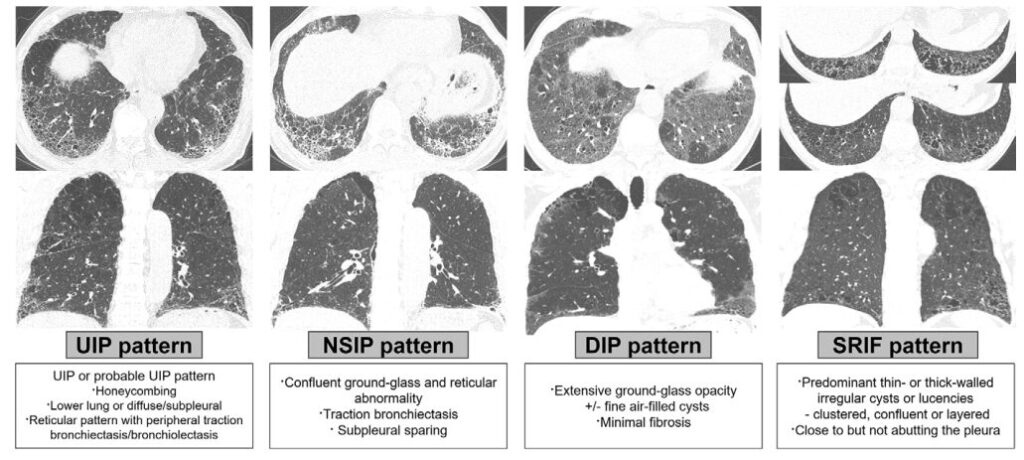

画像上の線維化パターンは、通常型間質性肺炎(usual interstitial pneumonia:UIP)および/またはprobable UIP(放射線学的UIP)と、それ以外(非特異性間質性肺炎[NSIP]、喫煙関連間質性線維化[SRIF]、剥離性間質性肺炎[DIP])に分類した。

236例中、UIP 99例(41.9%)、NSIP 73例(30.9%)、SRIF 48例(20.3%)、DIP 14例(5.93%)、分類不能2例(0.85%)であった。

UIP 41.9%、NSIP 30.9%、SRIF 20.3%、DIP 5.9%、分類不能0.85%。